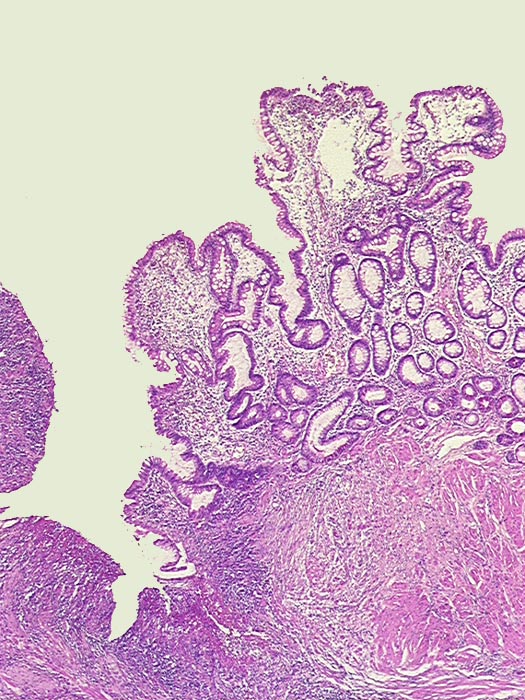

PathoPic ID 369 - Fissurales Ulkus bei floridem Morbus Crohn

Fissurales Ulkus bei floridem Morbus Crohn

Ileum terminal

Links das tiefreichende Ulkus. Rechts davon hyperplastische Dünndarmschleimhaut (makroskopisch Pflastersteinrelief).

Stenose des terminalen Ileums mit chronischem Subileus